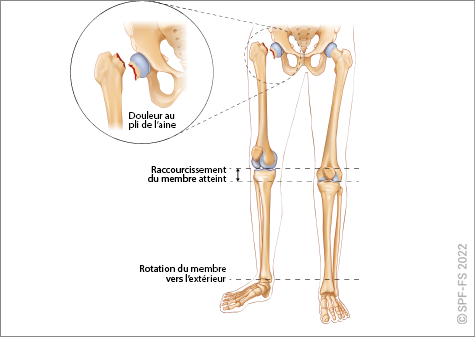

Le bassin

Le bassin osseux (ou pelvis) constitue la jonction entre la colonne vertébrale et les membres inférieurs. En forme d'entonnoir, plus large chez la femme que chez l'homme, il est composé par :

Figure 2-11 : les os du bassin

Les membres inférieurs

Les membres inférieurs sont chacun formés de trois segments :

Figure 2-13 : le membre inférieur

La hanche est l'articulation qui relie la cuisse au bassin. Le genou relie la cuisse à la jambe et la cheville la jambe au pied.

Ce dernier comporte cinq orteils numérotés de 1 à 5 de l'intérieur vers l'extérieur. Les phalanges sont numérotées de P1 à P3, dans le sens allant du talon vers l'ongle.

Figure 2-14 : coupe de l'articulation de la hanche